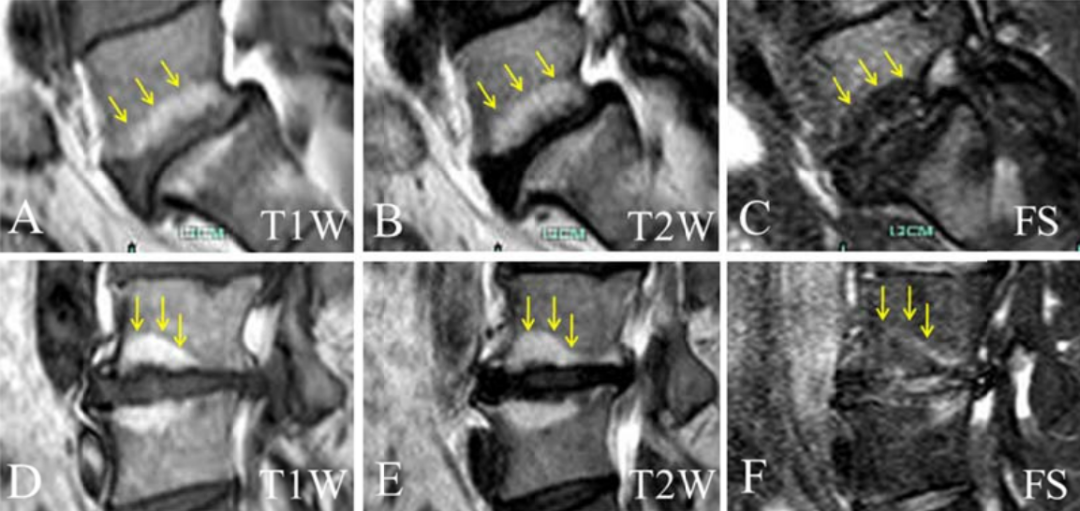

随后,Feng 等利用抑制像 MRI,回顾性分析 65 例 Ⅱ 型 Modic 改变(150 个终板)的腰痛患者 MRI 图像后发现,其中 75.3% 的终板在 T2 抑脂像上呈高信号,提示大多数 Ⅱ 型 Modic 改变存在局部水肿性病变。

Sun 等通过 CT 研究发现,Ⅱ 型 Modic 改变区域的 CT 值明显高于非病变区域,且相邻椎间盘退变越重,病变区域的 CT 值则越高。提示 Ⅱ 型 Modic 改变也存在骨硬化,且相邻椎间盘退变越重,骨硬化则越严重。